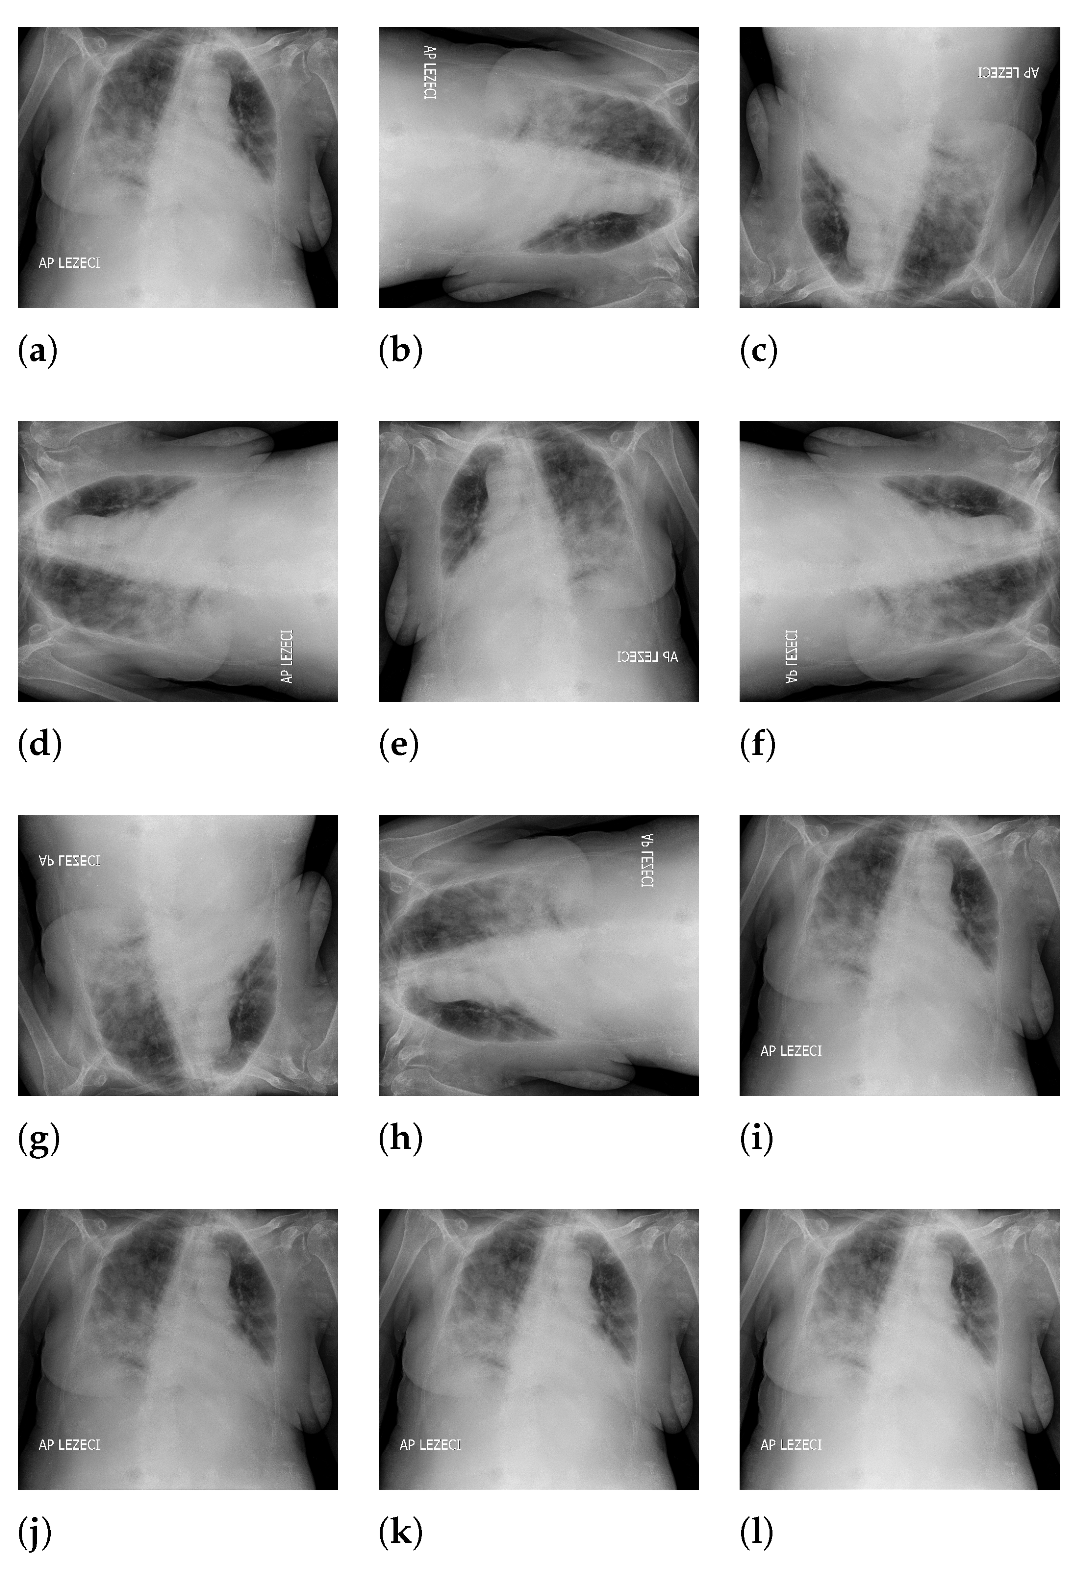

The 90-degree rotation presents an operation that rotates the original image (presented with Figure 3a) by 90 degrees in a clockwise direction around the sagittal axis, as presented in Figure 3b. Following the presented logic, rotations for 180 and 270 degrees were performed as well, as presented in Figure 3c,d. Images rotated by 90 and 270 degrees were resealed in order to have the same dimensions as the original image. Image generation by 180-degree rotation around the longitudinal axis was performed in such a way that the new image represented a mirrored projection of the original image, as presented in Figure 3e. The mirrored image was rotated around the sagittal axis, forming three new variations, as presented in Figure 3f–h. As the final approach to image augmentation, a process of multiplication of all image pixels with a certain factor is proposed. In this case, four different factors (0.8, 0.8, 1.1, and 1.2) were used. The described transformations have been presented on an original image with Figure 3i–l. It is important to notice that such transformations were applied on an augmented set that was created by using all described geometrical transformations. By using such an approach, the new augmented dataset was four times larger than the dataset created by using just geometrical transformations.

Figure 3. Overview of image augmentation procedure ((a): original image; (b): image rotated for 90 degrees around sagittal axis; (c): image rotated for 180 degrees around sagittal axis; (d): image rotated for 270 degrees around sagittal axis; (e): image rotated for 180 degree around longitudal axis; (f): image rotated for 180 degree around longitudal axis and rotated for 180 degree around sagittal axis; (g): image rotated for 180 degree around longitudal axis and rotated for 180 degree around sagittal axis; (h): image rotated for 180 degree around longitudal axis and rotated for 270 degree around sagittal axis; (i): image with pixels multiplied by a factor 0.8; (j): image with pixels multiplied by a factor 0.9; (k): image with pixels multiplied by a factor 1.1; (l): image with pixels multiplied by a factor 1.2).